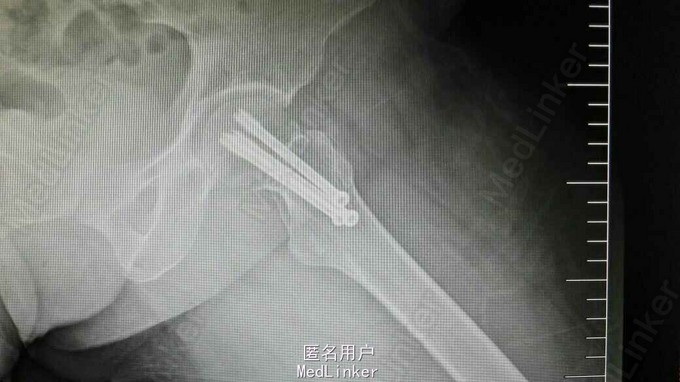

诊断:左股骨颈骨折(头下型,Garden IV期) 治疗:闭合牵引复位开心钉内固定术

术后早期扶拐杖左下肢不负重下地行走,3月后复查照片骨折愈合,有退钉现象,开始负重行走,无疼痛。术后2年复查骨折愈合,钉尾有退出同术后3月复查照片差别不大,患者无诉不适。建议拆除空心钉。 讨论:对于老年患者来说,认为股骨颈头下型骨折,Garden IV是全髋关节置换手术适应症,但对相对年轻患者做何种手术取舍教较困难,你怎么看?